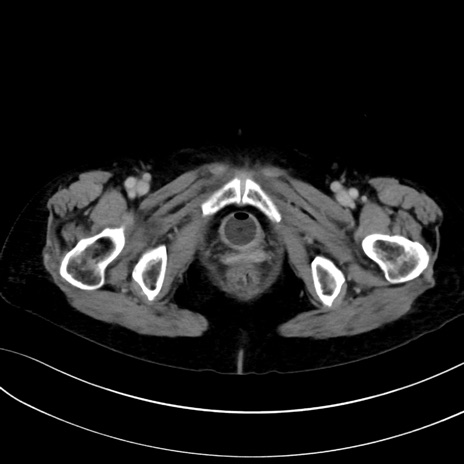

症例13 CT(横断像)1日半後